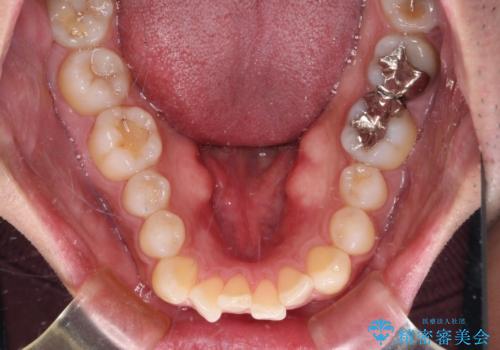

- 口元の突出感と下の前歯のがたつきを主訴として来院された患者様です。

口元の突出感と叢生改善のため上下左右の第一小臼歯4本を抜歯し、ワイヤー装置にて矯正治療を行うこととしました。

口元の突出感もなくなり満足されました。